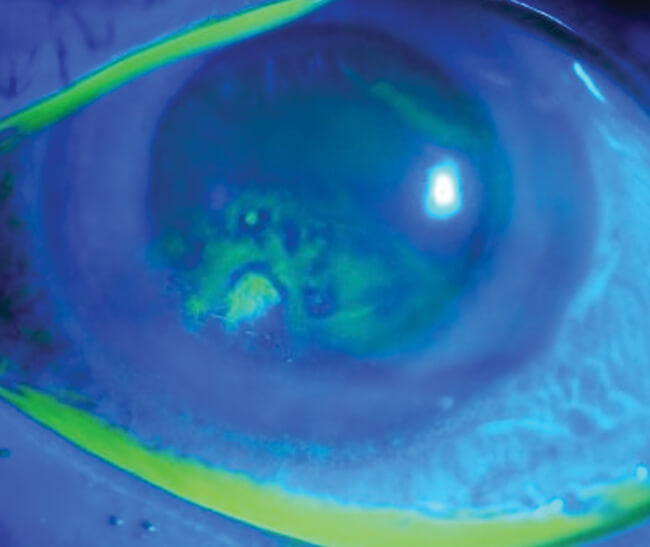

A 29-year-old woman awoke with a painful, red, watery left eye. The patient self-medicated with over the counter Hypromellose eye drops, every 30 minutes for one day, which resolved her symptoms. She did not seek any further medical attention. Two months later, the patient experienced the same symptoms, and presented to eye casualty. Slit-lamp examination with fluorescein staining, showed a left eye, 4mmx4mm corneal erosion. History noted the patient was taking Roaccutane (brand name of Isotretinoin) 80mg once daily, for four months. She was advised to use a hot compress every day, prescribed Hypromellose eye drops, VitA-POS eye ointment, and had follow-up in four weeks.

Within these four weeks, the patient had a further two episodes of waking overnight with left eye pain which resolved, on average, in 10 minutes. In the follow-up clinic, slit-lamp examination measured the erosion at 2.5mmx2.0mm with no infiltrate on the left cornea anteriorly, no anterior chamber reaction nor corneal oedema. The patient was advised to continue with regular Hypromellose and VitA-POS and in addition, Chloramphenicol eye drops, three times daily, for three days. Anterior stromal puncture and phototherapeutic keratectomy with excimer laser were discussed as treatment options, if symptoms persisted.

Figure 2: Fluorescein staining showing abnormal uptake suggestive of recurrent corneal erosion [16].